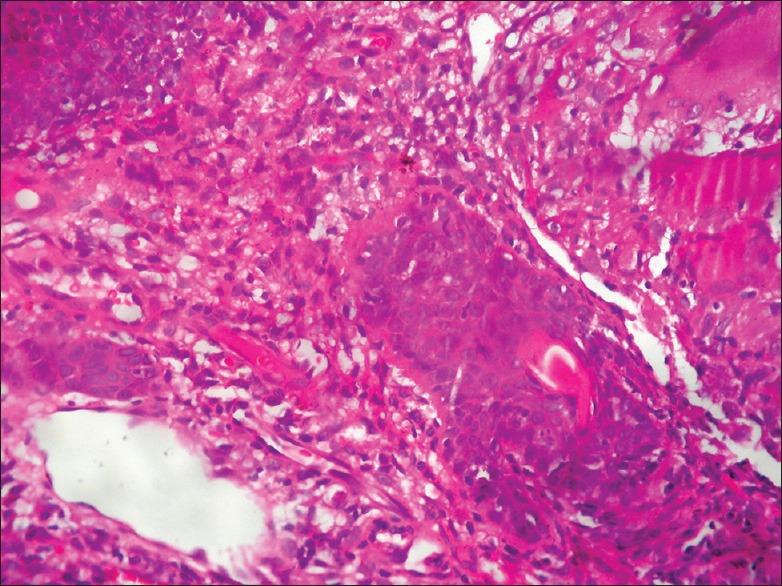

Ulcerative lupus vulgaris over nose, leading to cosmetic deformity.

Lupus vulgaris (LV), is a chronic and progressive form of secondary cutaneous tuberculosis. In India, it is commonly seen over buttocks, thighs, and legs whereas involvement of nose is quite rare. Ulcerative variant particularly over nose causes destruction of cartilage, leading to irreversible deformities and contracture. High-index of suspicion is required for early diagnosis and prevention of cosmetic deformity. A case of LV over nose in a young male with ulceration is reported who responded well to anti-tubercular therapy, but left with scarring of nose, which could have been prevented if adequate awareness regarding extra-pulmonary cases would have been practiced.